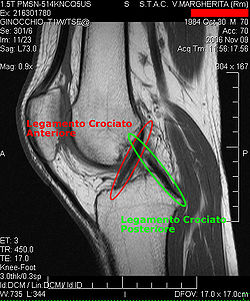

Procédés d'imagerie

Le diagnostic peut être confirmé par imagerie (IRM). Mais il faut noter que l'interprétation de l'IRM seule pour le diagnostic de rupture de LC conduit à 20 % de faux diagnostics. Cela dépend des images de coupe et de la position appropriée du genou pendant l'IRM. Le radiologue doit connaître avec précision les circonstances qui ont conduit à la blessure, et avoir aussi une bonne expérience de l'étude d'une articulation blessée, pour éviter les faux diagnostics. Pour comparer avec l'IRM, le taux d'erreur du test de Lachman, bien plus simple à accomplir, n'est que de 10 %[108],[109],[110],[111]. L'IRM est donc généralement moins sensible et moins spécifique que l'examen clinique par un orthopédiste qualifié[112]. Le résultat de l'IRM n'a que relativement rarement une influence sur la formulation finale du diagnostic[113] et ne devrait pas servir de remplacement pour une anamnèse soigneuse et la palpation[114]. Plusieurs études arrivent à la conclusion que l'IRM n'a de sens que pour des blessures complexes difficiles à expliquer, et là, pour éviter de poser un diagnostic négatif[115],[116],[117].